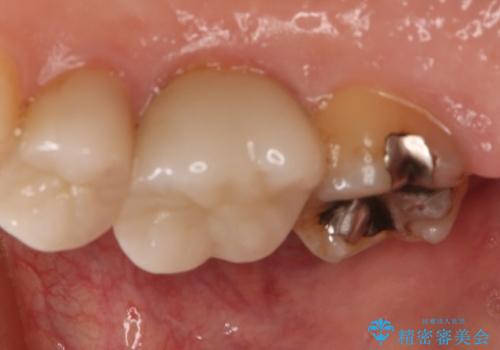

- 右上7番の銀歯のやりかえを主訴に来院された患者様です。

切削量・形態を考慮し、セラミックインレーでの治療を計画しました。

インレー治療では自分の歯を多く残すことが出来ます。